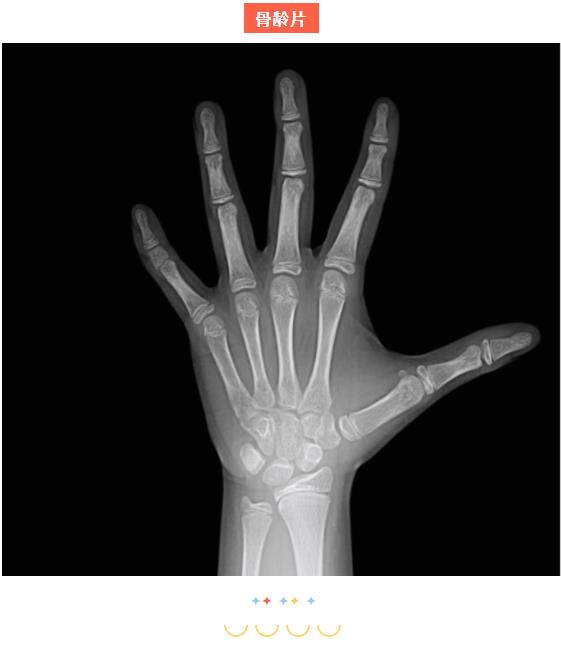

骨龄检查不但可以排查“早长“现象及导致孩子晚长的相关疾病,通过及时干预将对身高的不良影响降到最低,还可以通过对骨龄发育速度的合理调控来为孩子争取更多长高时间,助力孩子实现理想身高!3岁以上孩子建议定期检测骨龄,及时了解【长高潜能】。

身高管理的一项重要内容是提醒家长要关注和预防肥胖。营养过剩会导致骨龄加速发育,而忽视骨龄就会影响到终身高。身高管理门诊的当务之急是从营养角度控制儿童体重,调控骨龄发育速度,避免骨龄过早“发育”。最好的状态是,骨龄始终等于或低于生活年龄。

长高是一场倒计时,一旦生长板闭合

长高的机会就很小了